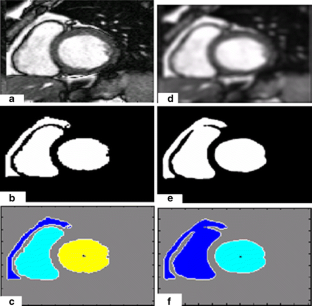

Segmentation of the left ventricle in MRI images is a task with important diagnostic power. Currently, the evaluation of cardiac function involves the global measurement of volumes and ejection fraction. This evaluation requires the segmentation of the left ventricle contour. In this paper, we propose a new method for automatic detection of the endocardial border in cardiac magnetic resonance images, by using a level set segmentation-based approach. To initialize this level set segmentation algorithm, we propose to threshold the original image and to use the binary image obtained as initial mask for the level set segmentation method. For the localization of the left ventricular cavity, used to pose the initial binary mask, we propose an automatic approach to detect this spatial position by the evaluation of a metric indicating object’s roundness. The segmentation process starts by the initialization of the level set algorithm and ended up through a level set segmentation. The validation process is achieved by comparing the segmentation results, obtained by the automated proposed segmentation process, to manual contours traced by tow experts. The database used was containing one automated and two manual segmentations for each sequence of images. This comparison showed good results with an overall average similarity area of 97.89%.

Fig. 4